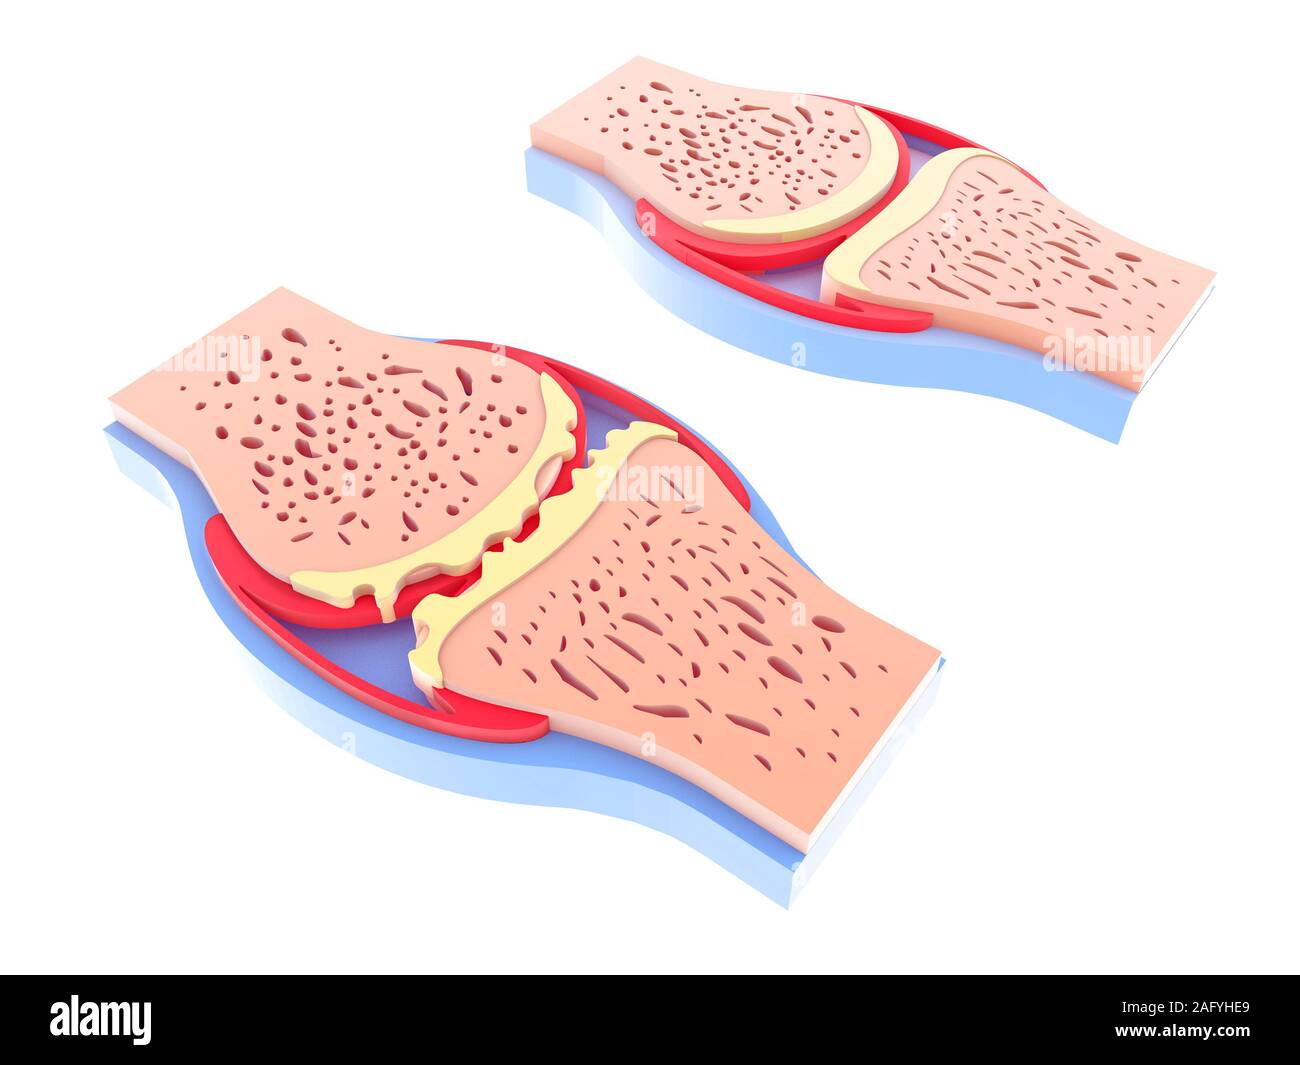

3d illustration of healthy and spherical synovial joint. In four representations standing and isolated on white background. Stock Photohttps://www.alamy.com/image-license-details/?v=1https://www.alamy.com/3d-illustration-of-healthy-and-spherical-synovial-joint-in-four-representations-standing-and-isolated-on-white-background-image336823258.html

3d illustration of healthy and spherical synovial joint. In four representations standing and isolated on white background. Stock Photohttps://www.alamy.com/image-license-details/?v=1https://www.alamy.com/3d-illustration-of-healthy-and-spherical-synovial-joint-in-four-representations-standing-and-isolated-on-white-background-image336823258.htmlRF2AFYHE2–3d illustration of healthy and spherical synovial joint. In four representations standing and isolated on white background.

3d illustration of healthy and spherical synovial joint. In four representations standing and isolated on white background. Stock Photohttps://www.alamy.com/image-license-details/?v=1https://www.alamy.com/3d-illustration-of-healthy-and-spherical-synovial-joint-in-four-representations-standing-and-isolated-on-white-background-image336823105.html

3d illustration of healthy and spherical synovial joint. In four representations standing and isolated on white background. Stock Photohttps://www.alamy.com/image-license-details/?v=1https://www.alamy.com/3d-illustration-of-healthy-and-spherical-synovial-joint-in-four-representations-standing-and-isolated-on-white-background-image336823105.htmlRF2AFYH8H–3d illustration of healthy and spherical synovial joint. In four representations standing and isolated on white background.